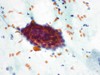

Critères cytologiques d’une LIEHG

(Lésion intra-épithéliale de haut grade)

- Atypies dans les cellules profondes/immatures (cellules de taille parabasale)

- Ratio N/C >50 %

- Contours nucléaires irréguliers encochés

- > 10 de cellules avec ces atypies

- Chromatine hyper, normo ou hypochrome

- Chromatine irrégulière

- Amas denses hyperchromes désordonnés de type parabasal (ASC-H)